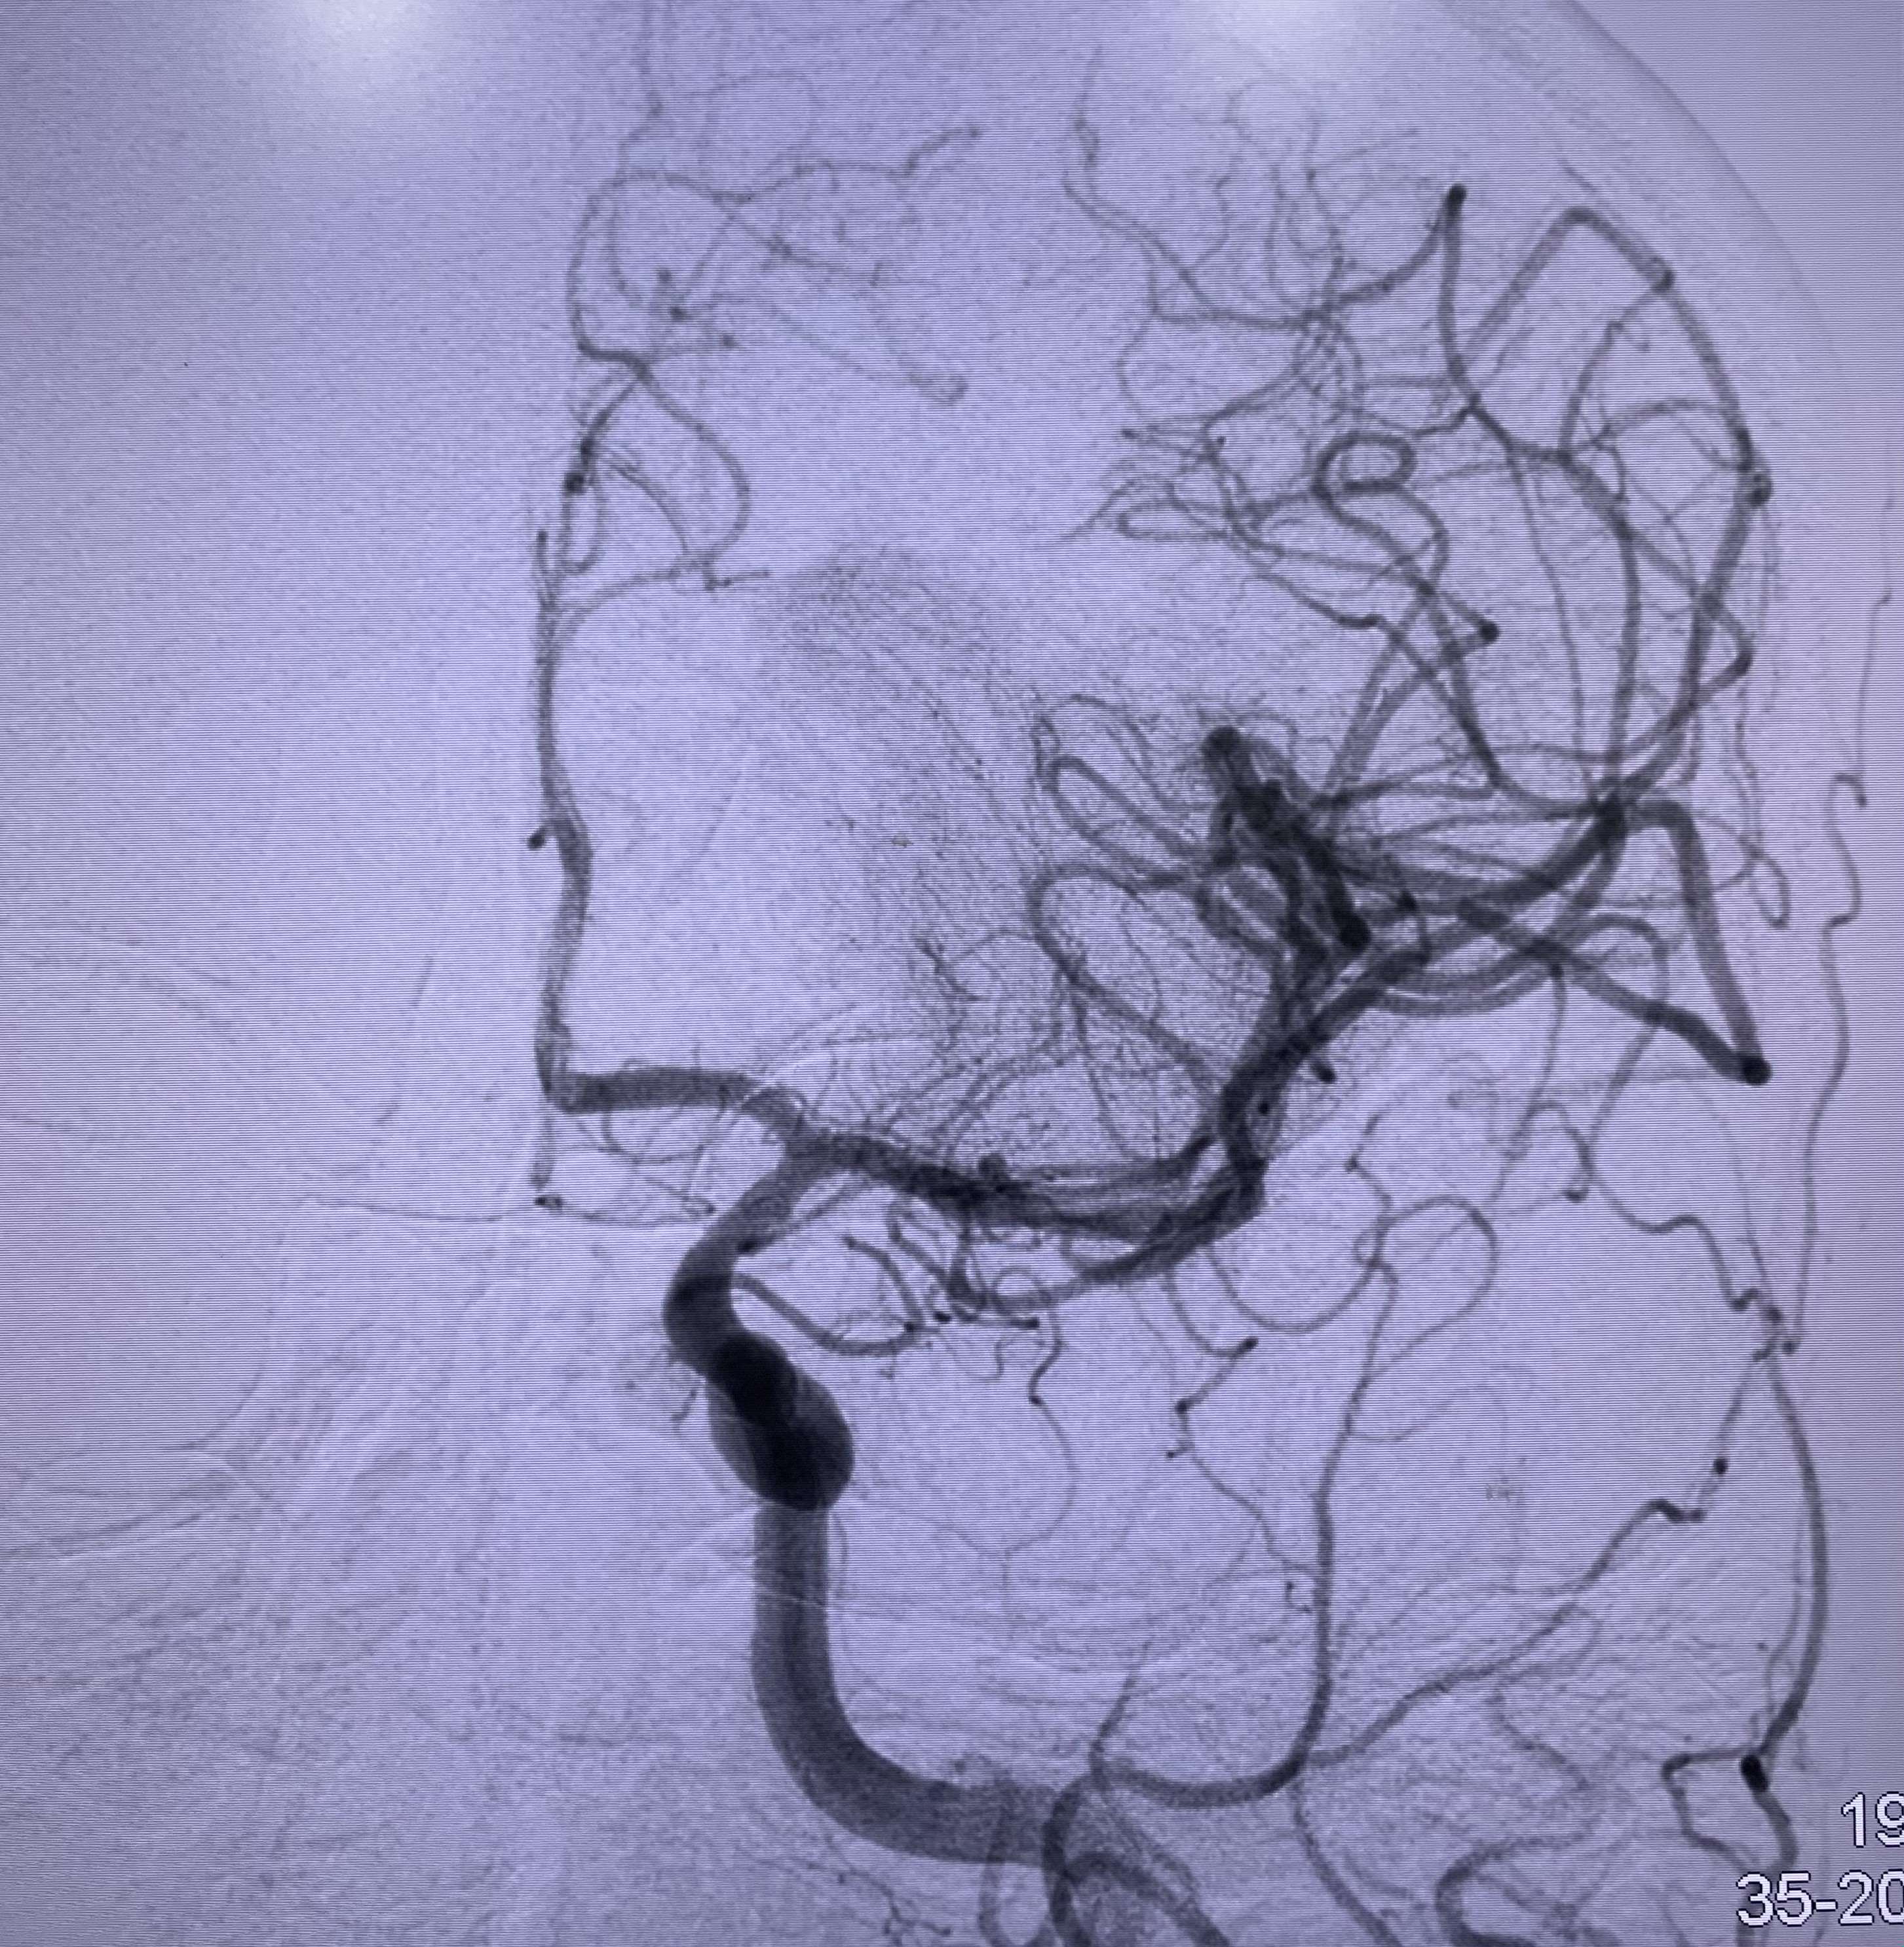

Promptly after admission, the patient received immediate treatment through intravenous thrombolysis with a dosage of 30 mg of tenecteplase. Subsequently, a mechanical thrombectomy procedure was conducted, employing a RED 72 reperfusion catheter (Penumbra). Following 2 passes of the catheter, a resilient clot was successfully retrieved. This intervention resulted in the complete recanalization of the MCA, leading to full perfusion of the entire left MCA territory (modified treatment in cerebral infarction score of 3, a successful recanalization). Notably, during digital subtraction angiography, an incidental finding revealed a shelf-like filling defect within the left carotid bulb, which was subsequently identified as a carotid web (Figures 3, 4, and 5).